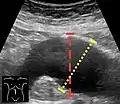

An abdominal aortic aneurysm is usually diagnosed by physical exam, abdominal ultrasound, or CT scan. Plain abdominal radiographs may show the outline of an aneurysm when its walls are calcified. However, the outline will be visible by X-ray in less than half of all aneurysms. Ultrasonography is used to screen for aneurysms and to determine their size if present. Additionally, free peritoneal fluid can be detected. It is noninvasive and sensitive, but the presence of bowel gas or obesity may limit its usefulness. CT scan has nearly 100% sensitivity for an aneurysm and is also useful in preoperative planning, detailing the anatomy and possibility for endovascular repair. In the case of suspected rupture, it can also reliably detect retroperitoneal fluid. Alternative less often used methods for visualization of an aneurysm include MRI and angiography.